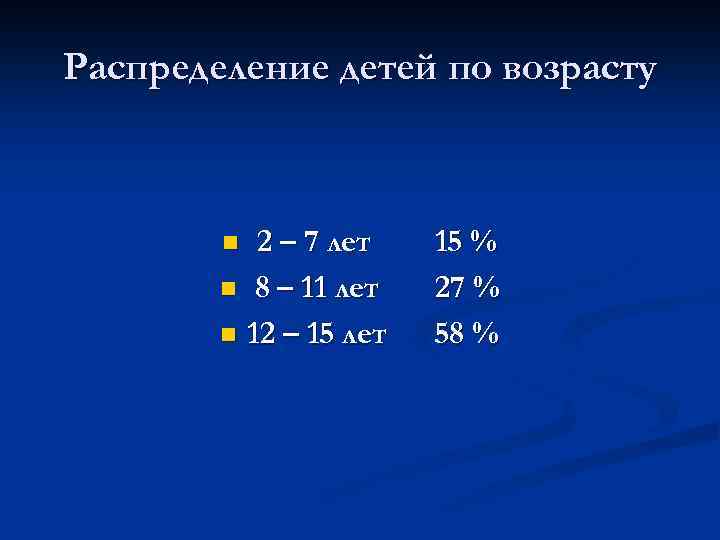

Распределение детей по возрасту 2 – 7 лет n 8 – 11 лет n 12 – 15 лет n 15 % 27 % 58 %